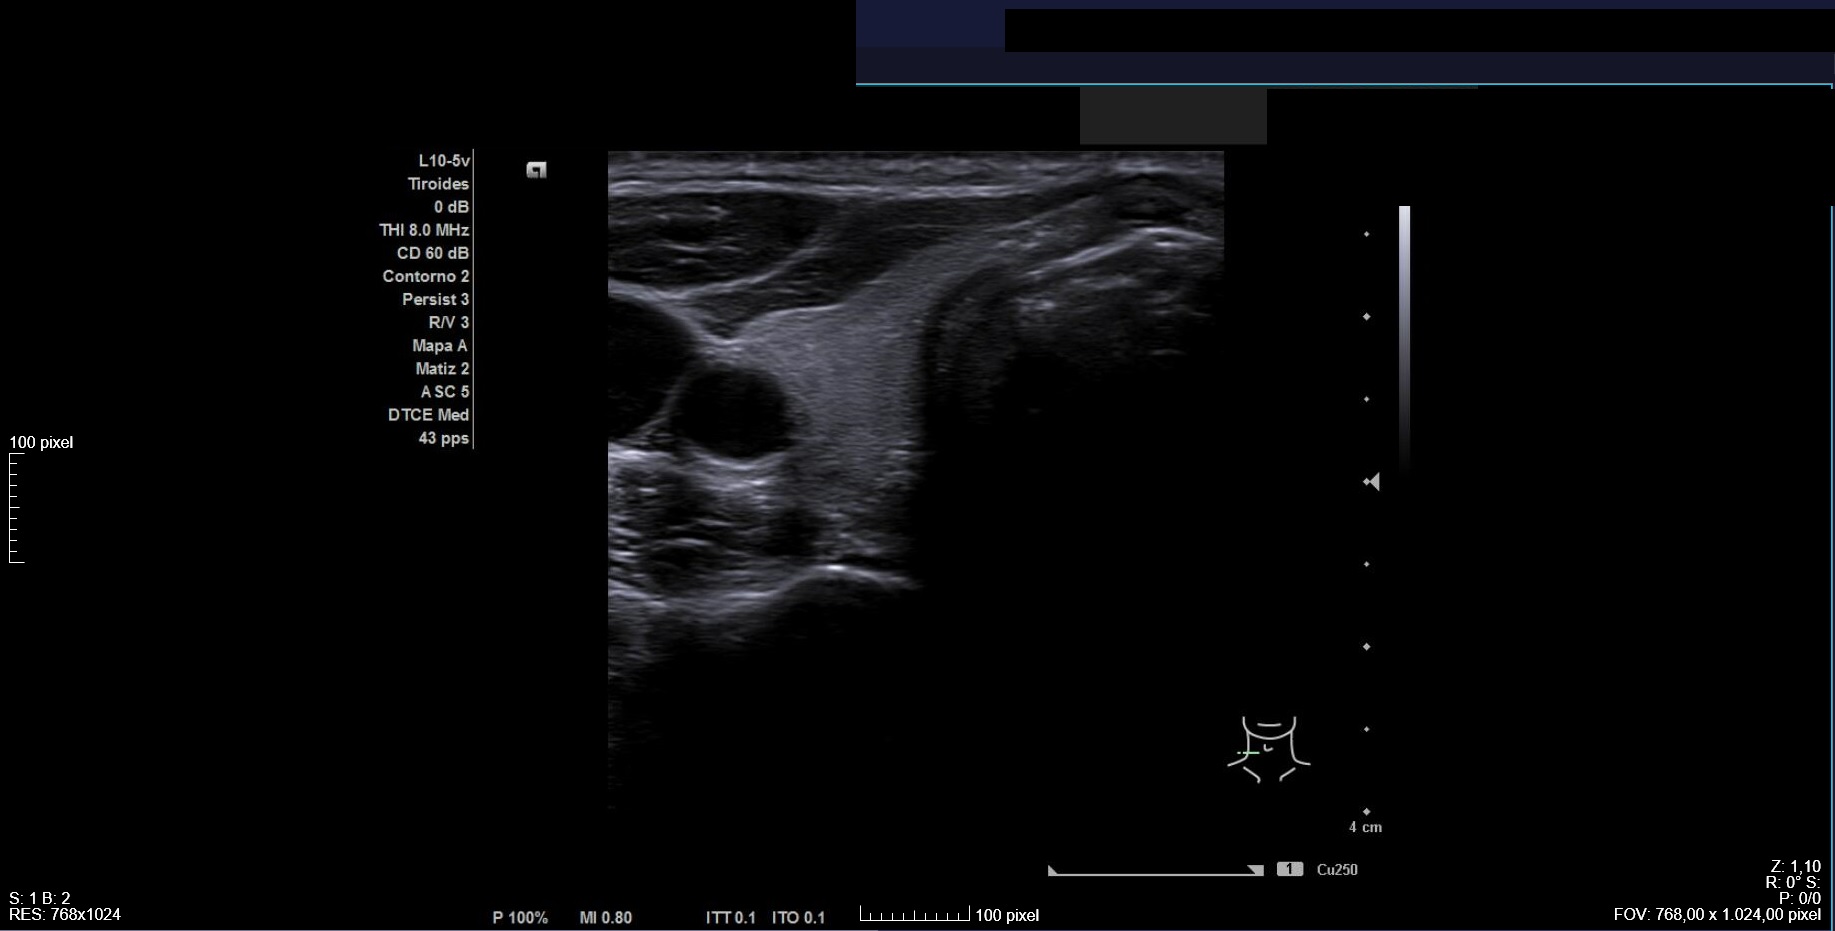

Citamos para seguimiento clínico-ecográfico dos meses después. El bulto había tenido una evolución fluctuante en tamaño pero habían reaparecido las molestias. Nueva ecografía (Imagen 4) confirmó nódulo de características similares a las iniciales, de tamaño ligeramente inferior (2,1 x 2,3 cm). Se observaban focos ecogénicos puntiformes y ecogenicidad indeterminada (TIRADS=4).

Realizamos interconsulta a Endocrinología para valorar PAAF con objetivo diagnóstico-terapéutico.